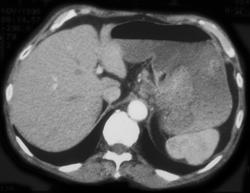

Pseudomyxoma Peritonei (PMP)